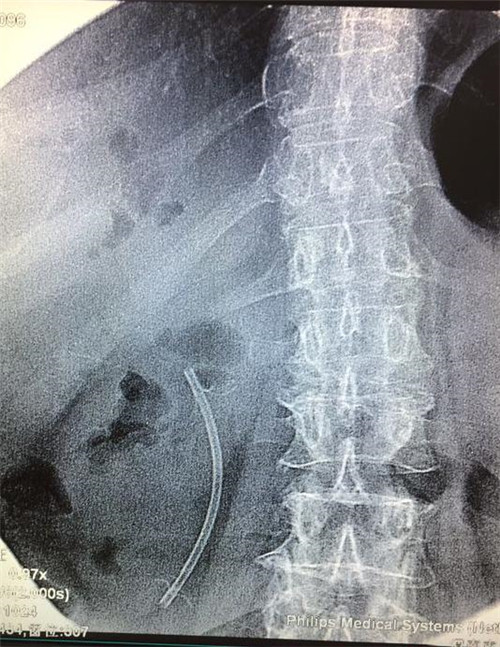

经过多个科室的配合,在介入科X线机下,曹鹏医生于十二指肠镜下顺利将导丝插入患者胆管内,注入二氧化碳气体造影,X线下见患者肝内外胆管扩张,胆管末端明显有占位性病变,患者胆管末端因肿瘤压迫,非常狭窄,经过多级扩张后,顺利为患者置入胆道支架。手术非常顺利,患者生命体征平稳,大家都松了口气。